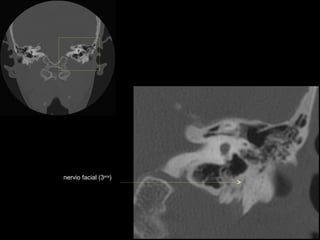

CATEDRA DE RADIOLOGIA U.N.L.P.   Hueso temporal normal        Edición 2002

celdillas mastoideas

eminencia piramidal

seno timpánico

receso del n. facial

nervio facial (3era)